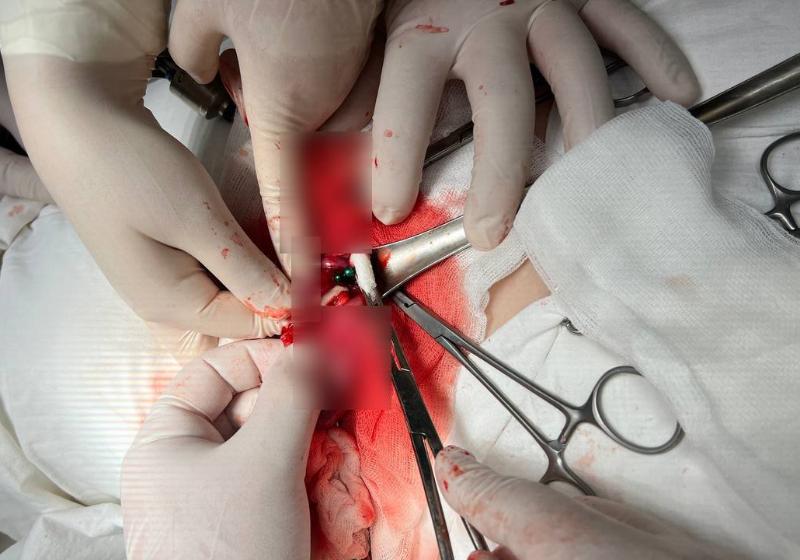

Ситуация потребовала перехода к открытой операции. Через разрез передней брюшной стенки хирурги получают доступ к органам брюшной полости. В ходе вмешательства обнаружили и устранили тяжелейшие последствия: ушили образовавшиеся межкишечные свищи, удалили участок тонкой кишки с перфорацией размером до 2 см. Отдельная опасность заключалась в том, что часть магнитов опустилась в аппендикс, который также пришлось удалить. Объем выполненного хирургического вмешательства отражает всю сложность случая.